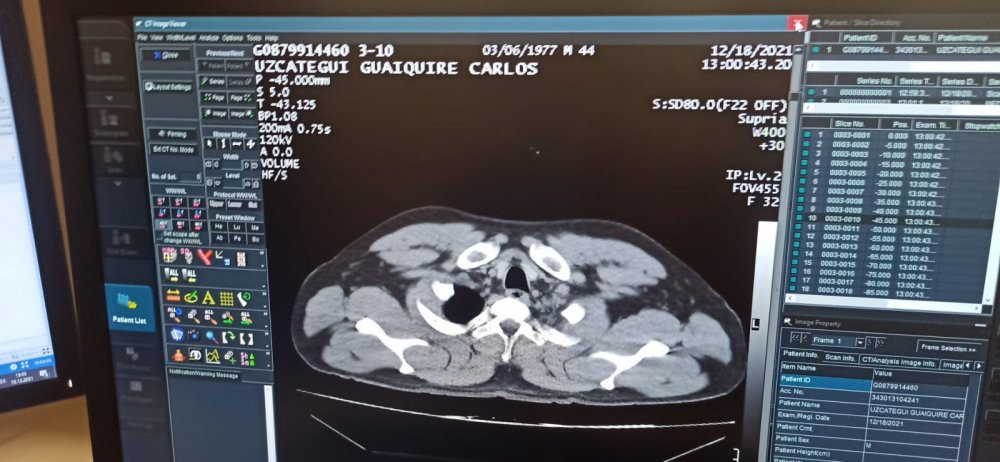

C.M.U.G'un hastanede yapılan tomografi kontrolünde mide ve bağırsaklarında 12 adet kapsül kokain tespit edilmesini üzerine, ameliyata alındı.